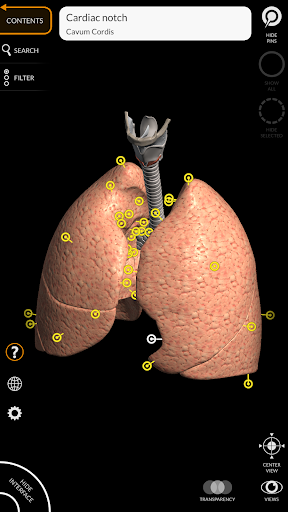

"Anatomy 3D Atlas" memungkinkan Anda mempelajari anatomi manusia dengan cara yang mudah dan interaktif.

Melalui antarmuka yang sederhana dan intuitif, Anda dapat mengamati setiap struktur anatomi dari sudut mana pun.

Model 3D anatomi sangat terperinci dan memiliki tekstur hingga resolusi 4k.

MODEL ANATOMI 3D

saraf • Sistem pernapasan • Sistem pencernaan • Sistem urogenital (pria dan wanita) • Sistem endokrin • Sistem limfatik • Sistem mata dan telinga FITUR • Antarmuka yang sederhana dan intuitif • Putar dan perbesar setiap model dalam ruang 3D • Opsi untuk menyembunyikan atau mengisolasi satu atau beberapa model yang dipilih • Filter untuk menyembunyikan atau menampilkan setiap sistem • Fungsi pencarian untuk menemukan setiap bagian anatomi dengan mudah • Fungsi penanda untuk menyimpan tampilan khusus • Rotasi cerdas yang menggerakkan pusat rotasi secara otomatis • Fungsi transparansi • Visualisasi otot melalui tingkat lapisan dari yang superfisial hingga yang terdalam • Dengan memilih model atau pin, istilah anatomi terkait akan muncul • Deskripsi otot: asal, • Tampilkan/ Sembunyikan antarmuka UI (sangat berguna dengan layar kecil) MULTIBAHASA • Istilah anatomi dan antarmuka pengguna tersedia dalam 11 bahasa: Latin, Inggris, Prancis, Jerman, Italia, Portugis, Turki, Rusia, Spanyol, Mandarin, Jepang, dan Korea • Istilah anatomi dapat ditampilkan dalam dua bahasa secara bersamaan PERSYARATAN SISTEM • Android 8.0 atau yang lebih baru, perangkat dengan RAM minimal 3GB Reversi

• Sistem pernapasan